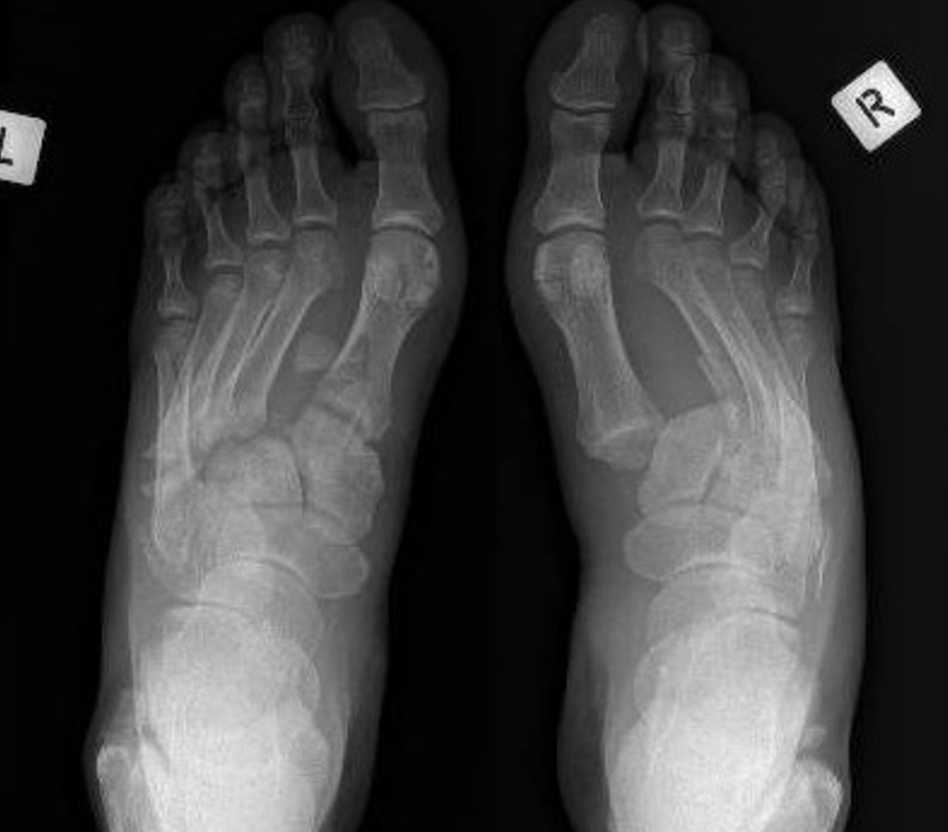

The Lisfranc or tarsometatarsal joints refer to the middle of the foot. This area is critical to supporting the foot's arch. Please see Foot - Anatomy and Imaging to understand more.

Lisfranc injuries involve soft-tissue (ligament tears) and/or bone (fractures) damage that disrupt this important area (see 3D CT image).

Diagnosis of Lisfranc Midfoot Injury

- imaging investigations.